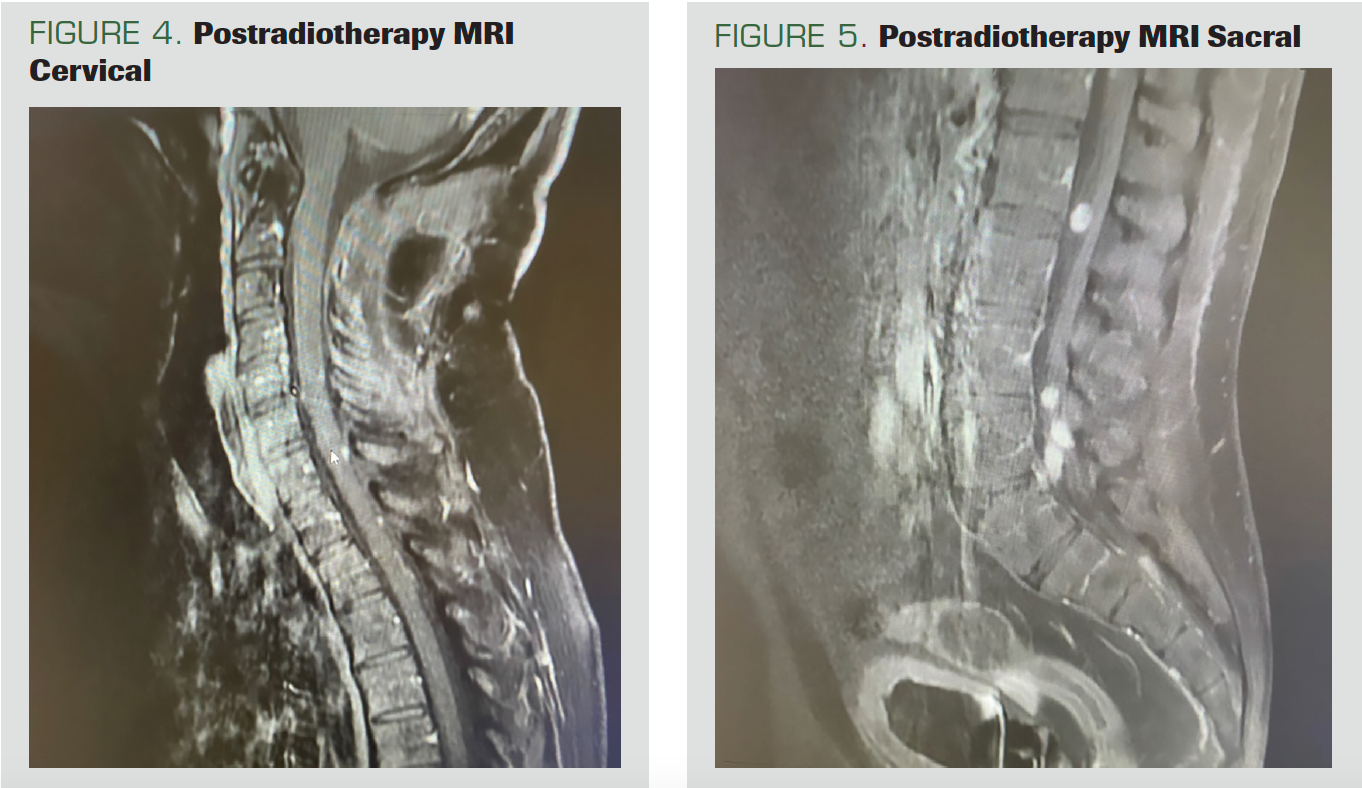

The patient, who came to the control after 2 months, had no adverse effects. No residual disease was found on the cervical MRI (Figure 4). However, nodular-shaped tumoral implants, all smaller than 1 cm, were noted on the spinal cord surface. Continuity of the implants was observed, starting from the distal thoracic spine segments on the thoracic, lumbar, and sacral MRIs and continuing up to the conus, suggesting the leptomeningeal spread of the existing tumor. In addition, leptomeningeal implants of neoplastic nature, the largest of which was approximately 1.1 cm in diameter, were observed within the fibers of the cauda equina in the distal conus medullaris (Figure 5).

FIGURE 4. Postradiotherapy MRI Cervical

FIGURE 5. Postradiotherapy MRI Sacral